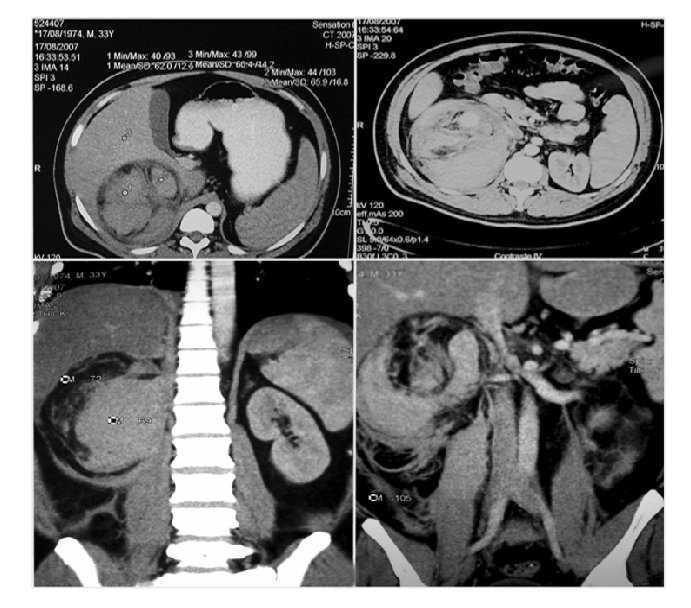

Una vez en mejor estado general se realizó tomografía axial computarizada que mostró una imagen de un tumor renal derecho de 10 UH heterogéneo que desplazaba en sentido posteroinferior y medial al riñón (Imagen 1). Las dimensiones del tumor fueron de 15 cm en sentido longitudinal y 10 cm en sentido transversal, de características heterogéneas con un refuerzo de -30 UH al administrar medio de contraste, lo que aumentó la sospecha de angiomiolipoma renal. Se realizó resonancia magnética con reconstrucción vascular, en la cual se observó hiperintensidad en T1, isointensidad en T2, sin delimitar el tumor y con sangrado con dimensión aproximada de 6-7 cm de diámetro (Imagen 2). En la angiorresonancia se observó pobre vasculatura, incrementando la sensibilidad diagnóstica para angiomiolipoma (Imagen 3).

Imagen 2. RM fase T1 y T2.